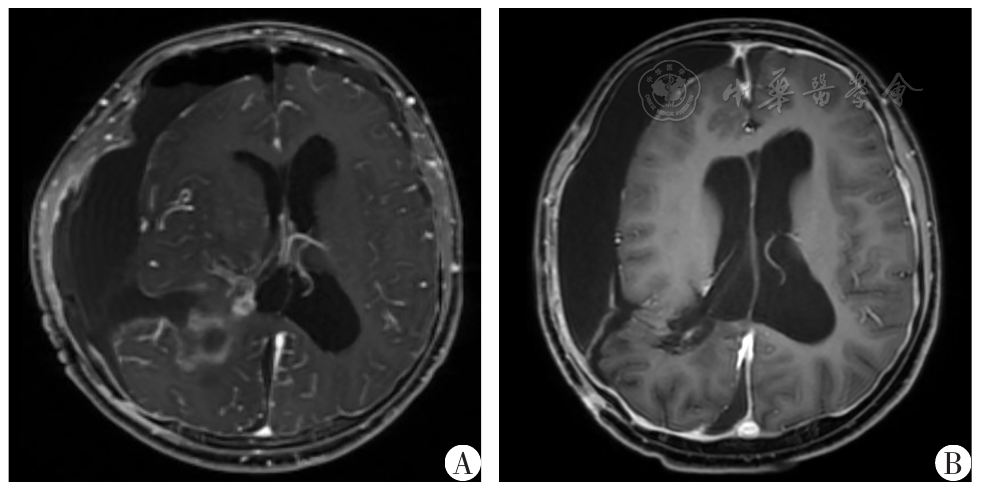

图3 颅内巨大脑膜瘤患儿术后MRI资料A:术后7 d增强T1WI;B:术后2个月增强T1WI

Fig.3 Preoperative and postoperative MRI dating of a child with intracranial giant meningioma